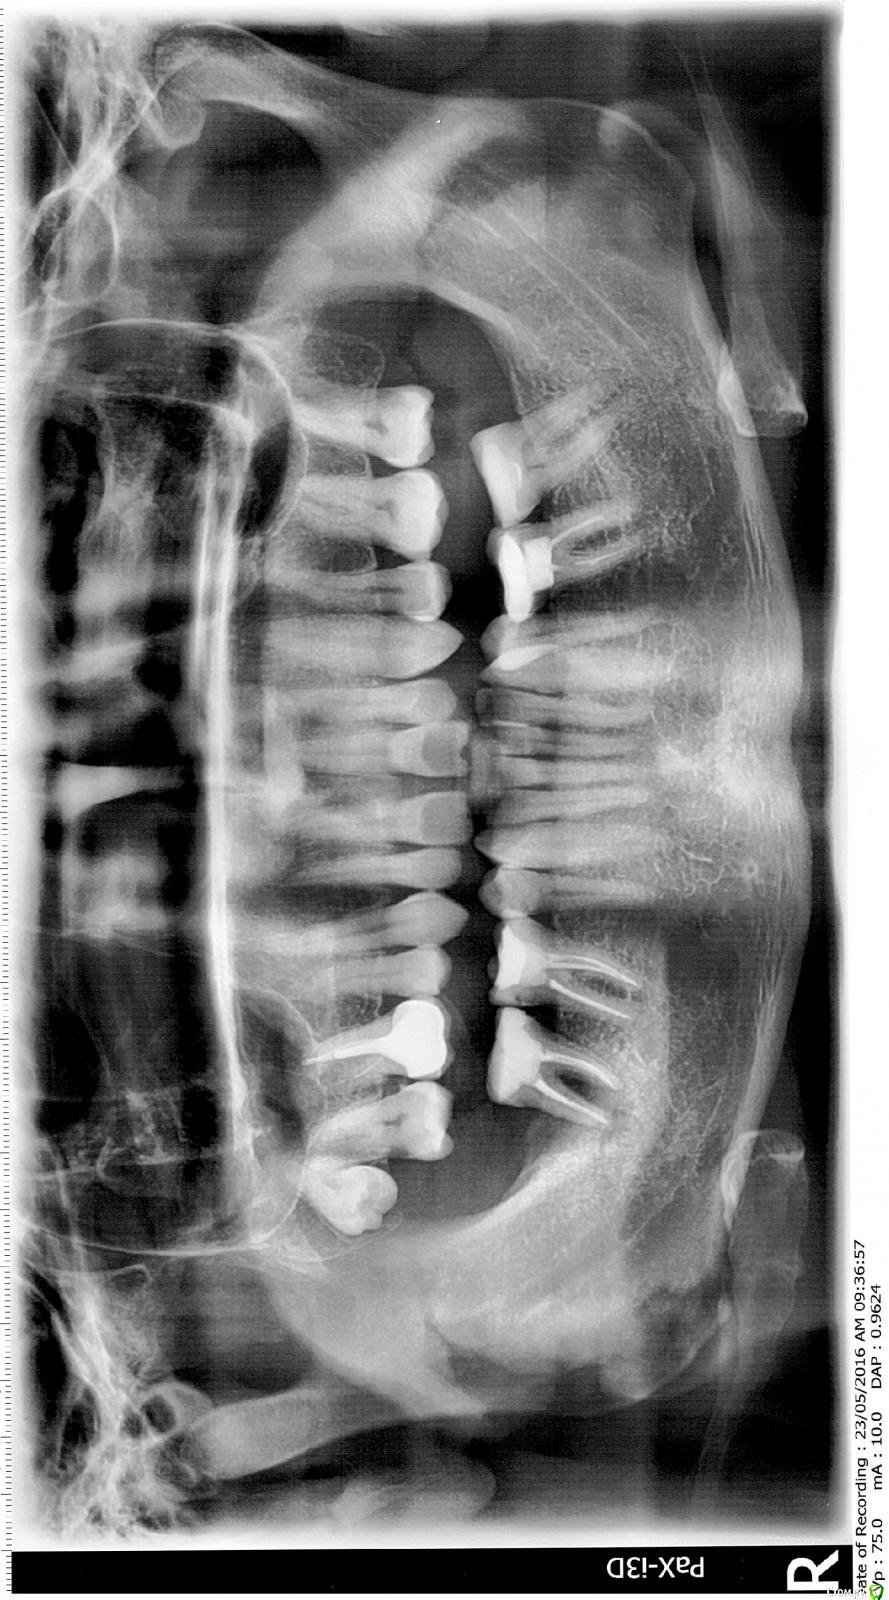

Slava76 Опубликовано 24 мая, 2016 Автор Поделиться Опубликовано 24 мая, 2016 Снимок Ссылка на комментарий

red_butler Опубликовано 24 мая, 2016 Поделиться Опубликовано 24 мая, 2016 Эх, не жалеете Вы наши шеиhttp://s020.radikal.ru/i719/1605/1e/dbb40810295d.jpgПосмотреть бы конечно во рту и покрутить Кт, что бы понять причину. Если проблема только в лечении корневого канала, и нет трещины/перфорации, то побороться за зуб можно. Но если хотите гарантированный результат, то удаляйте. Ссылка на комментарий

vse32 Опубликовано 24 мая, 2016 Поделиться Опубликовано 24 мая, 2016 подождем что ответят терапевты, но я какой либо связи патологии прикуса и проблемы с седьмым зубом не увидел. Однозначно что решать проблему нужно, или терапевтически или терапевтически.Если прикус не правильный, то с начала исправление, и потом имплантация и постоянное протезирование.Так там бифуркация "пустая". Такое не лечится, увы. Либо терпеть, либо удаление. Не вижу способа улучшить ситуацию, кроме как удаление. Ссылка на комментарий

vse32 Опубликовано 24 мая, 2016 Поделиться Опубликовано 24 мая, 2016 А терпеть не опасно? Все таки на десне постоянный свищ, хоть он и не болит. И если не удалить зуб кость действительно будет дальше разрушаться? Да будет. Для соседних он пока не угроза, а вот если сильно оттянуть удаление - то в этой области будет большой костный провал. Ссылка на комментарий

red_butler Опубликовано 24 мая, 2016 Поделиться Опубликовано 24 мая, 2016 Так там бифуркация "пустая". Такое не лечится, увы. Либо терпеть, либо удаление. Не вижу способа улучшить ситуацию, кроме как удаление.Если проблема связана только с эндодонтом, то лечится. Во врачебном много успешных кейсов выложено. Ссылка на комментарий